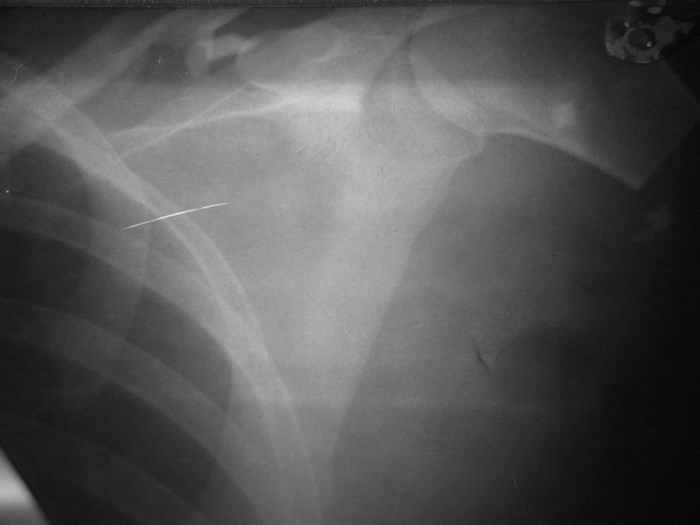

У больной З. 26 лет, пострадавшей в результате ДТП (08.08.05.), имеется травматическая ампутация левой верхней конечности на уровне проксимального отдела плечевой кости,

закрытый оскольчатый перелом левой ключицы со смещением отломков.В ургентном порядке произведено ПХО раны с формированием культи конечности.В настоящее время (22.09.05) культя без признаков воспаления, Выделений не отмечается, заживление полное. Имеются умеренные фантомные боли, особенно во второй половине дня, с ощущением лучезапястного и локтевого суставов.В настоящее время решается вопрос о сроках и методах протезирования конечности.

Фоторентгенограмма при поступлении и внешний вид больной на момент выписки прилагаются.